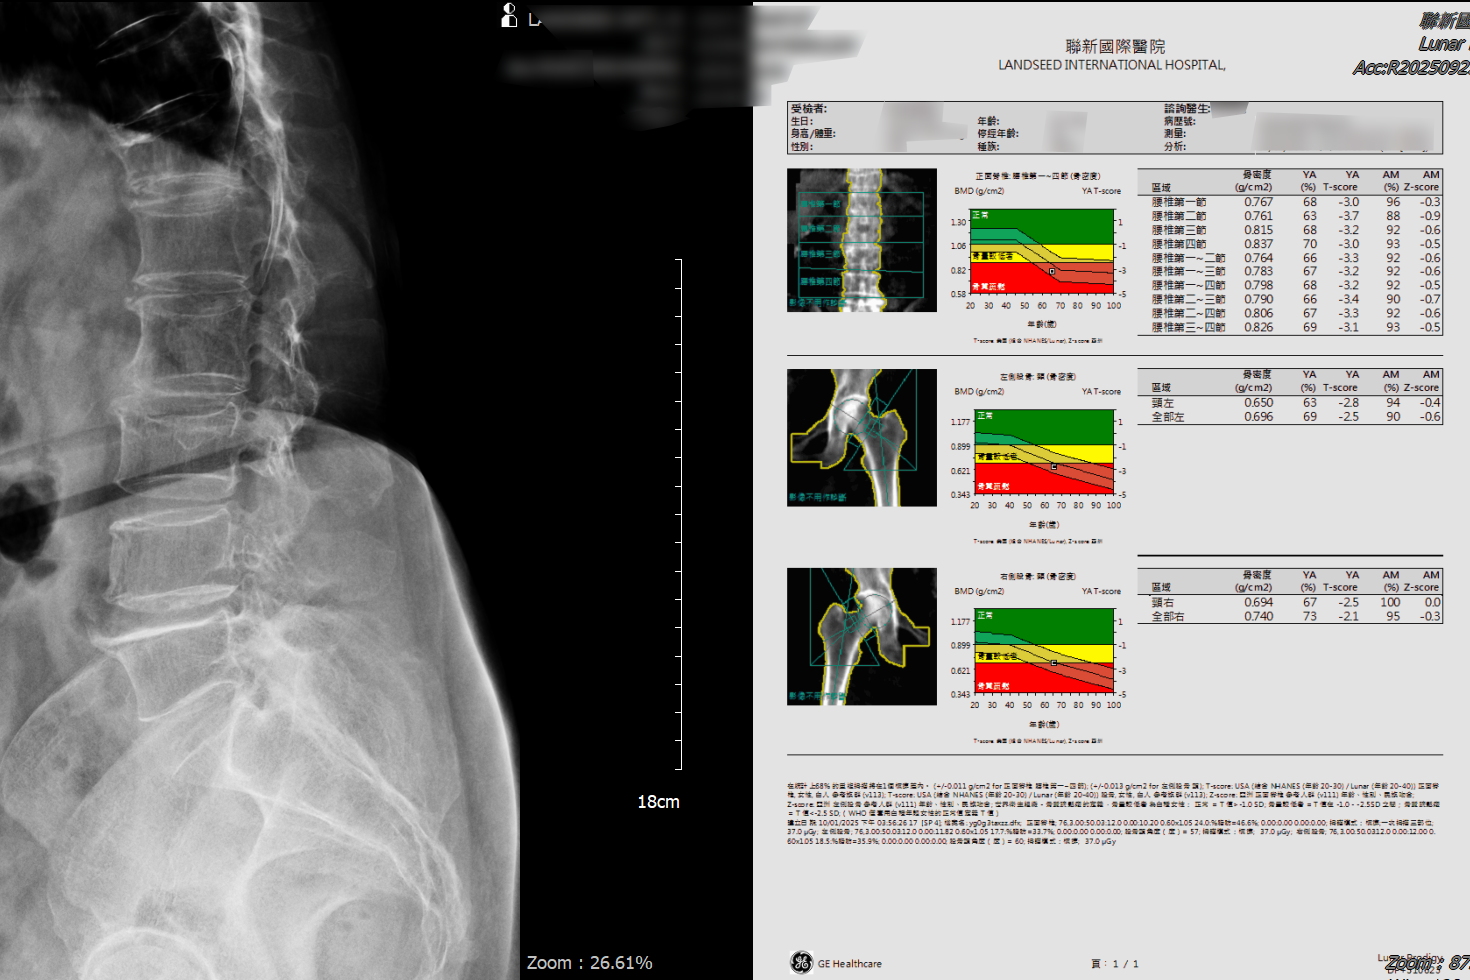

黃淳邦指出,目前診斷骨質疏鬆症最準確的方式為雙能量X光吸收儀,以腰椎與兩邊髖骨的骨密度T值為標準,T值介於-1至-2.5之間的民眾已出現骨質缺失的現象,可透過日常飲食跟運動去防止骨質繼續流失,一旦骨密度T值低於-2.5,即是罹患骨質疏鬆症。